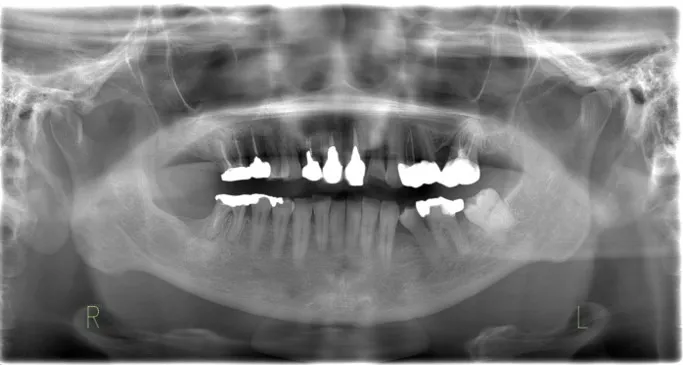

右下7:歯根嚢胞、右下8:埋伏智歯